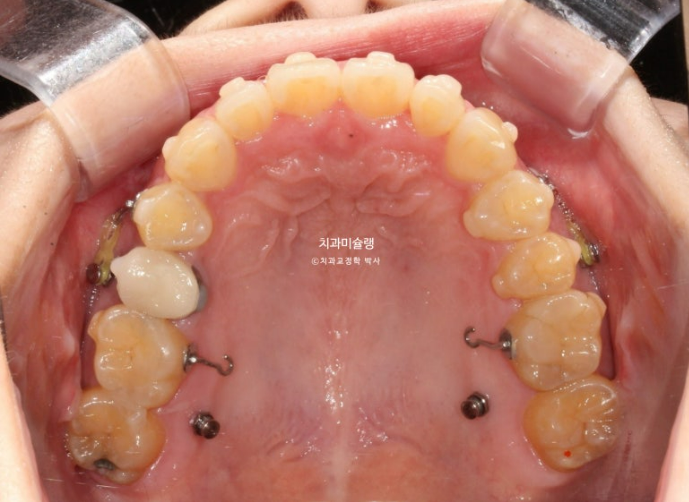

24.06

아래 앞니 두 개 잇몸이 유독 내려가 있습니다.

정중선 기준 한쪽만 개방교합이 있는데 한쪽방향으로 혀내밀기 습관때문에 생긴 개방교합일 수 있고 유지장치 변형에 의해 치열이 일그러진 것 일수도 있습니다.

소구치에 윗니와 아랫니가 엇갈려 물리는 가위교합도 보입니다.

큰어금니 교합도 좋은 편 입니다.

파란화살표는 가위교합 원인 치아입니다.

어금니를 뒤로 밀기위한 교정용 나사도 심고 진행합니다.

현재는 주로 뺐다 꼈다 하는 고무줄 처방을 하지만 환자분의 장치착용 협조도가 좋은 경우 치아에 직접 거는 고무로도 후방이동이 가능합니다.

25.02

어금니들이 사랑니 공간으로 순서대로 이동하며 공간이 생기는 중입니다.

안으로 쓰러졌던 작은어금니는 공간이 충분히 만들어 진 후 세우는 중입니다.